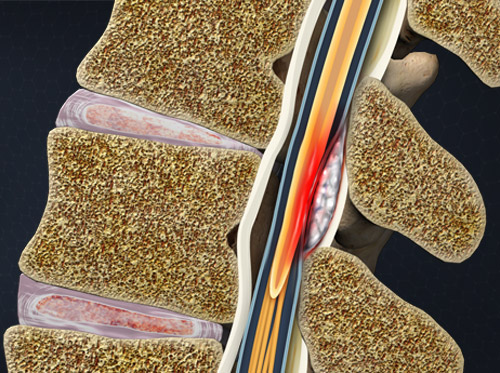

Una de las complicaciones más temidas es el absceso peridural, una entidad infecciosa que se caracteriza por la acumulación localizada de pus en el espacio epidural, el cual se sitúa entre la duramadre espinal y las estructuras óseas de la columna vertebral. Este espacio anatómico, que normalmente actúa como un amortiguador para la médula espinal y las raíces nerviosas, puede convertirse en un entorno propicio para la proliferación bacteriana cuando se rompe la barrera de esterilidad durante un procedimiento invasivo.

El mecanismo patogénico del absceso peridural en el contexto de un bloqueo regional se basa, generalmente, en la inoculación directa de microorganismos al espacio epidural a través de una técnica no completamente estéril o mediante la migración de patógenos desde la piel o el ambiente. También es posible que la infección se origine por diseminación hematógena desde un foco distante, aunque esto es menos frecuente. La instalación de una infección en esta área puede desencadenar una respuesta inflamatoria local severa, que al aumentar la presión dentro del canal espinal compromete el flujo sanguíneo medular y provoca isquemia de las neuronas. Esta cascada patológica puede conducir a déficits neurológicos de rápida progresión si no se interviene de forma oportuna.